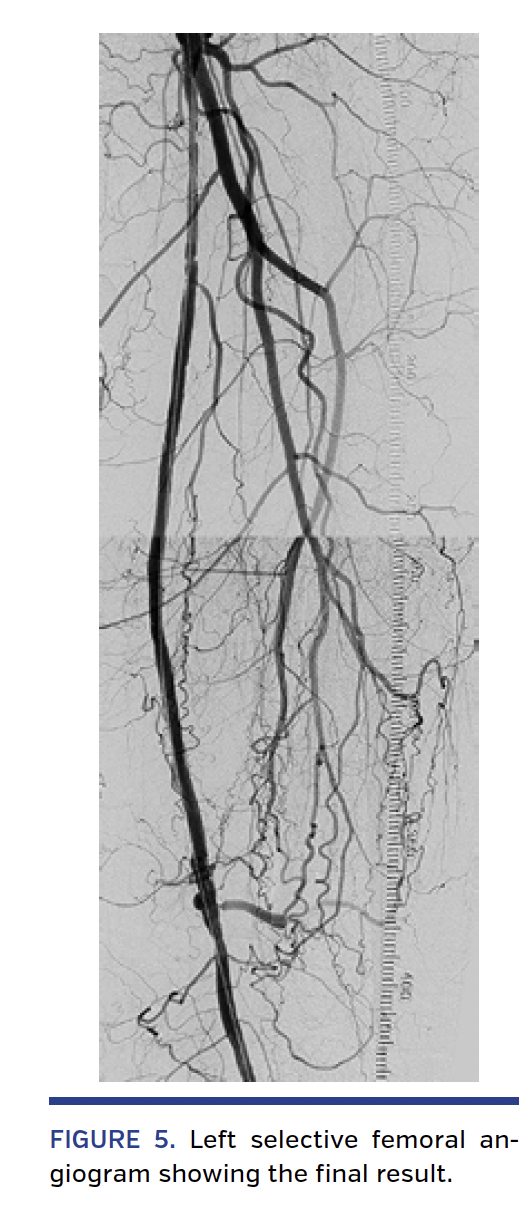

Procedure description. First, from a retrograde right femoral access, standard diagnostic angiograms were obtained, and a 6 Fr, 45 cm contralateral sheath was advanced to the level of the left common femoral artery. A selective angiogram showed a 20 cm-long SFA occlusion with a widely patent popliteal artery and 2-vessel run-off (Figure 3). A “tap” test was performed with a 0.018˝ Bentson wire (Boston Scientific) backed with a 5 Fr angled catheter with the distal tip placed in the proximal SFA just above the proximal cap of the CTO. This confirmed a fibrous “hard” CTO. The catheter and wire were then exchanged for a 4 x 100 mm Sterling balloon (Boston Scientific) advanced at the site of the CTO. The ShockWire was introduced into the balloon catheter. A second unsuccessful tap test was performed with the inactivated ShockWire. After activation of the ShockWire, the proximal cap and the first 2 cm of the occlusion were easily crossed. The inactivated ShockWire was then advanced through several centimeters of the occlusion. In the middle third of the 20 cm-long CTO, three areas of resistance were encountered despite repeated attempts to cross with the inactivated ShockWire. All three areas were readily crossed within 10 seconds of ShockWire activation. After crossing the entire length of the CTO, an angiogram was performed showing the tip of the ShockWire in the subintimal space adjacent to the distal cap. After removing the ShockWire, the wire was reinserted into the balloon catheter with a short bend at its distal tip (~2 mm, 45°). The ShockWire was then oriented toward the true lumen, and after activation, reentry was readily achieved (Figure 4). The balloon catheter was then advanced distal to the CTO, and the ShockWire was exchanged for a workhorse 0.018˝ wire. After predilation, the CTO was treated with 5 mm-long drug-coated balloons according to standard technique with an excellent angiographic result and no complications (Figure 5).